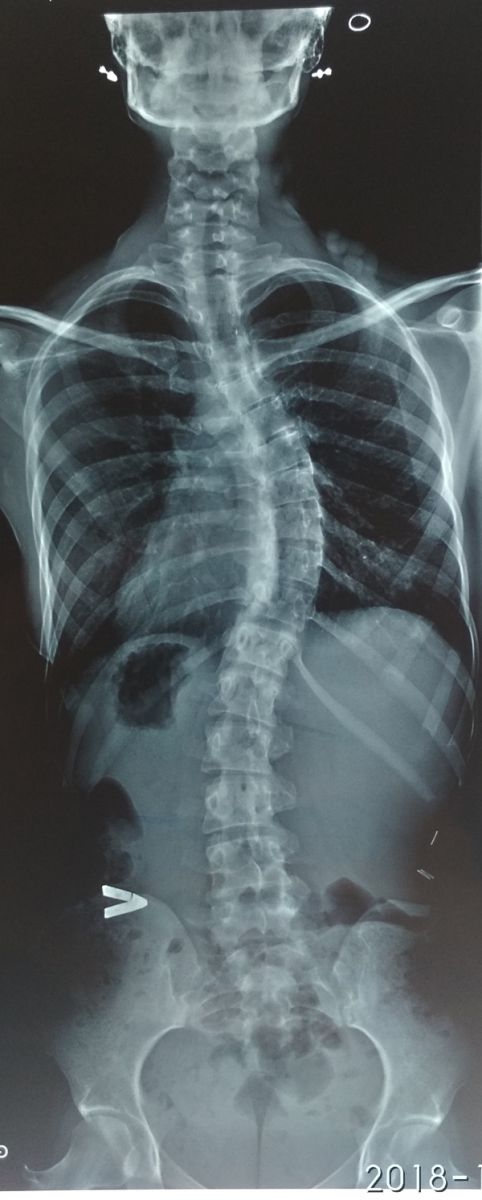

В зависимости от локализации изгиба различают сколиоз грудной, поясничный и смешанный, а также левосторонний и правосторонний. По форме искривление бывает С-образным, S-образным, Z-образным.

В зависимости от угла деформации различают 4 степени патологии:

- первая — менее 10°;

- вторая — 10-19°;

- третья — 20-39°;

- четвертая — более 40°.

- рентгенографию;